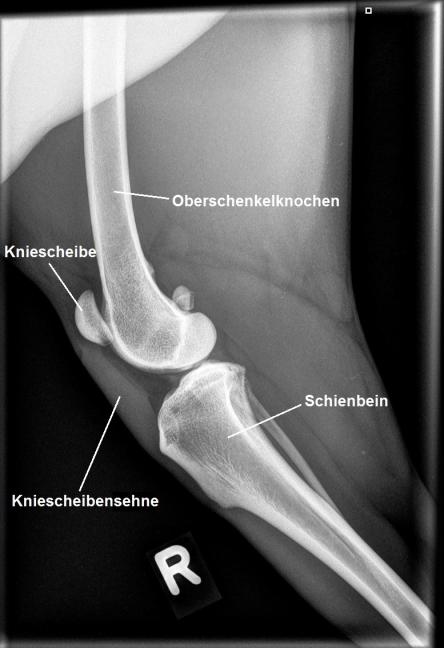

Erneut wird das verletzte Knie untersucht: Die beiden Hautwunden scheinen schön zu heilen, allerdings lässt sich nun feststellen, dass die Kniescheibensehne deutlich verdickt und schmerzhaft ist und sich weicher anfühlt als die Sehne im linken Knie. Die Patellarsehne (Ligamentum Patellae) zieht von der Kniescheibe zum Schienbein und ermöglicht dem Oberschenkelmuskel das Knie zu strecken. Röntgenaufnahmen der beiden Knie bestätigen, dass die Sehne stark verdickt ist. Unklar bleibt, ob sie gerissen oder nur stark überdehnt ist - in ersterem Fall muss das Problem zwingend chirurgisch angegangen werden. Wir überweisen Adlin deshalb zu einem MRT an eine Spezialistenklinik.

Für die Funktion des Hinterbeines ist die Sehne von zentraler Bedeutung: Sie überträgt die Kraft des grossen Oberschenkelmuskels (Quadriceps) via der "Umlenkrolle" Kniescheibe an den Schienbeinkopf und erlaubt so die Streckung des Knies. Reisst die Sehne, so ist der Hund nicht mehr in die Lage, über das Bein Kraft auszuüben, wodurch es funktionslos wird. In diesem Fall ist die chirurgische Reparatur des Risses zwingend.